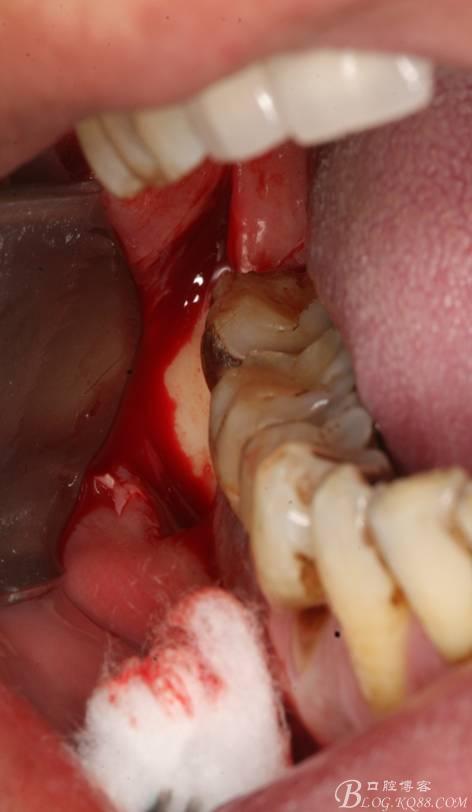

2.切開翻瓣

3.去骨、暴露48.

4. 縱分牙根和牙冠